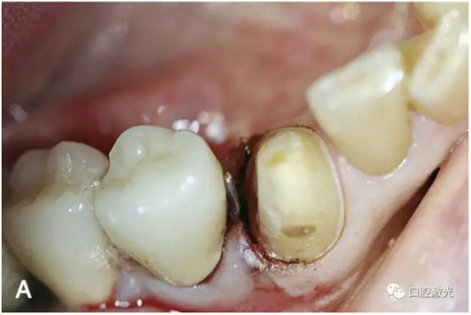

排齦是指使牙齦組織回縮,發(fā)生側(cè)向、垂直向位移,暴露出牙體預(yù)備完成線,創(chuàng)造一個(gè)清潔、干燥、無滲出的手術(shù)視野,以便制取印模。

口腔激光在固定修復(fù)中的應(yīng)用